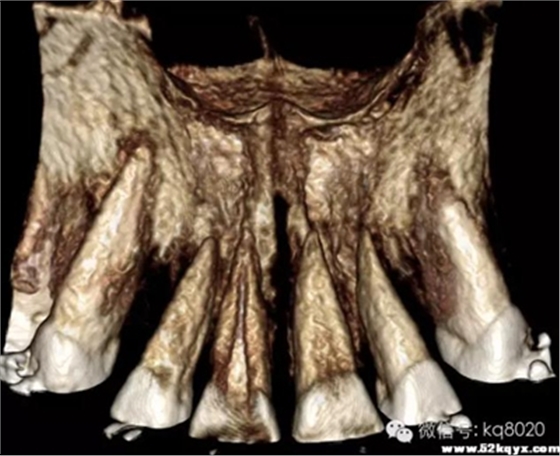

上下頜前牙區(qū)(11、12或者23之間,具體根據(jù)CT和患者頜關(guān)系決定):

危險(xiǎn)因素:此處無重要血管神經(jīng),相對(duì)安全,但牙根間距較小,避免傷及牙根植入位置和角度:應(yīng)從膜齦聯(lián)合處或其牙合方植入,大約距離牙槽嵴頂5-6mm的位置,

原因

①此處牙根間隔最大;

②避免植入后粘膜覆蓋;支抗釘位于牙根之間,與牙體長(zhǎng)軸成30-45°角

大?。河捎谇把绤^(qū)牙根間距小,骨質(zhì)疏松,宜選用6×1.4mm,且無切削尖設(shè)計(jì)支抗釘